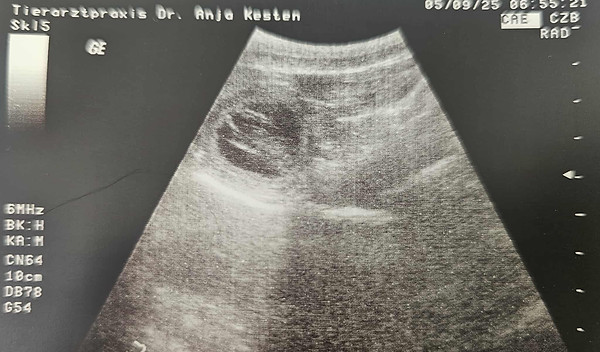

05.09.2025 (Tag 29): Der Ultraschall hat meine Vermutung bestätigt. Mooie ist trächtig und somit werden in ca. 5 Wochen kleine MoVi´s geboren.

25.09.05.jpg